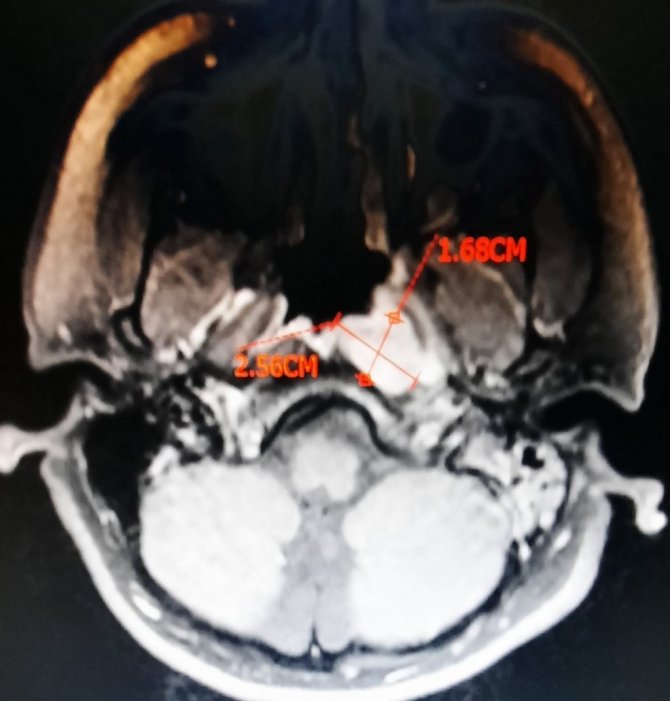

Hastanın yutkunmada dahi zorluk çektiğini ve birçok hastaneye başvurduğunu belirten Dr. Kenar; "Hastalarımızdan bahsedecek olursak, hastamızın biri 80 yaşında burun tıkanıklığı ve yutma güçlüğüyle bize başvurdu. Daha önceki gittiği hastanelerde bir takım tedaviler almış ama şikayetleri geçmeyince bize başvurduğunda, ileri yaştaki hastamızın burun tıkanıklığı şikayetine yönelik ilk etapta endoskopi ile baktık ve genzinde büyük bir kitle gördük. Genzini tamamen tıkayan, yutkunmasını dahi zorlaştıran tümör kitlesini kapalı (endoskopik) burun ameliyatıyla olabildiğince küçültüp aldık, patolojiye yolladık. İncelemeler sonucunda geniz kanseri teşhisi konuldu. Hastamız halen kemoterapi ve radyoterapi ile tedavisine devam etmektedir" ifadelerini kullandı.

Bu kanserin yaş fark etmeksizin her grupta görülebileceğini belirten Dr. Kenar; "Diğer hastamızın yaşı nispeten küçük ,16 yaşında. Bu hastamız bize tek taraflı işitme kaybı ile başvurdu. Burada bir kez tedavi verdik, normalde iyileşmesi lazım o yaşlarda işitme kaybının tedaviyle, ancak hastamızın şikayetinde hiçbir düzelme olmayınca, olası bir geniz eti varlığı için, ucu ışıklı kamerayla geniz muayenesi yaptığımızda genzinde özellikle sol tarafı tıkayan bir kitle gördük. Bu kitleyi tama yakın olabildiğince çıkarıp açıklığını sağladık. Hem de östaki borusu açıldı, kulağı havalanmaya başladı. Aynı seansta kulağına havalandırma tüpü de taktık. Gönderdiğimiz parçanın patolojisi geniz kanseri çıkması sonucunda da hastamıza kemoterapi ve radyoterapi almak üzere Onkoloji Bölümüne yönlendirdik. Şu anda hastalarımız tedavilerine başladılar. Geniz kanseri açısından uyanık olmak, şüphelenmek ve gerekli muayeneleri yapmak üzere kulak burun boğaz hekimine başvurmakta fayda olacağını düşünüyorum" şeklinde konuştu.